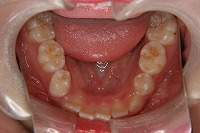

下顎 | ![]() |

![]() |

反対咬合を主訴に来院された、右側唇顎裂の10歳6ヵ月の女の子です。診断「右側唇顎口蓋裂で反対咬合を伴う」1期治療で反対咬合の解消と上顎の前歯の並びを修正しました。2期治療は抜歯をせず治療を行いました。